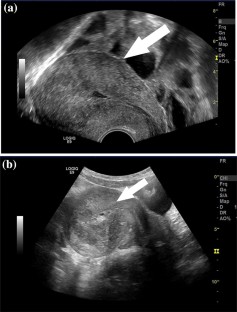

Fig. 1

Fig. 2

Fig. 3

Fig. 4

Fig. 5

Fig. 6